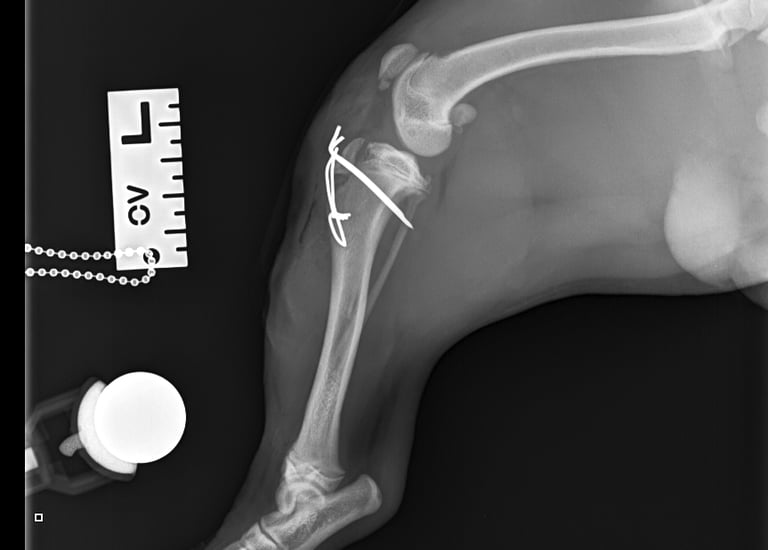

Lateral radiographs revealed a complete avulsion of the left tibial crest (Fig. 1), along with a mild lesion at the distal pole of the patella. For comparison, a lateral view of the right limb is included, demonstrating a normal appearance of the tibial crest growth plate (Fig. 2).

Surgical repair was performed using a medial approach to the proximal tibia. The avulsed tibial tuberosity fragment was identified, anatomically repositioned, and stabilized with two 1.2 mm Kirschner pins and a 1 mm tension band wire (Figs. 3 and 4).

Fig. 1

Fig. 3